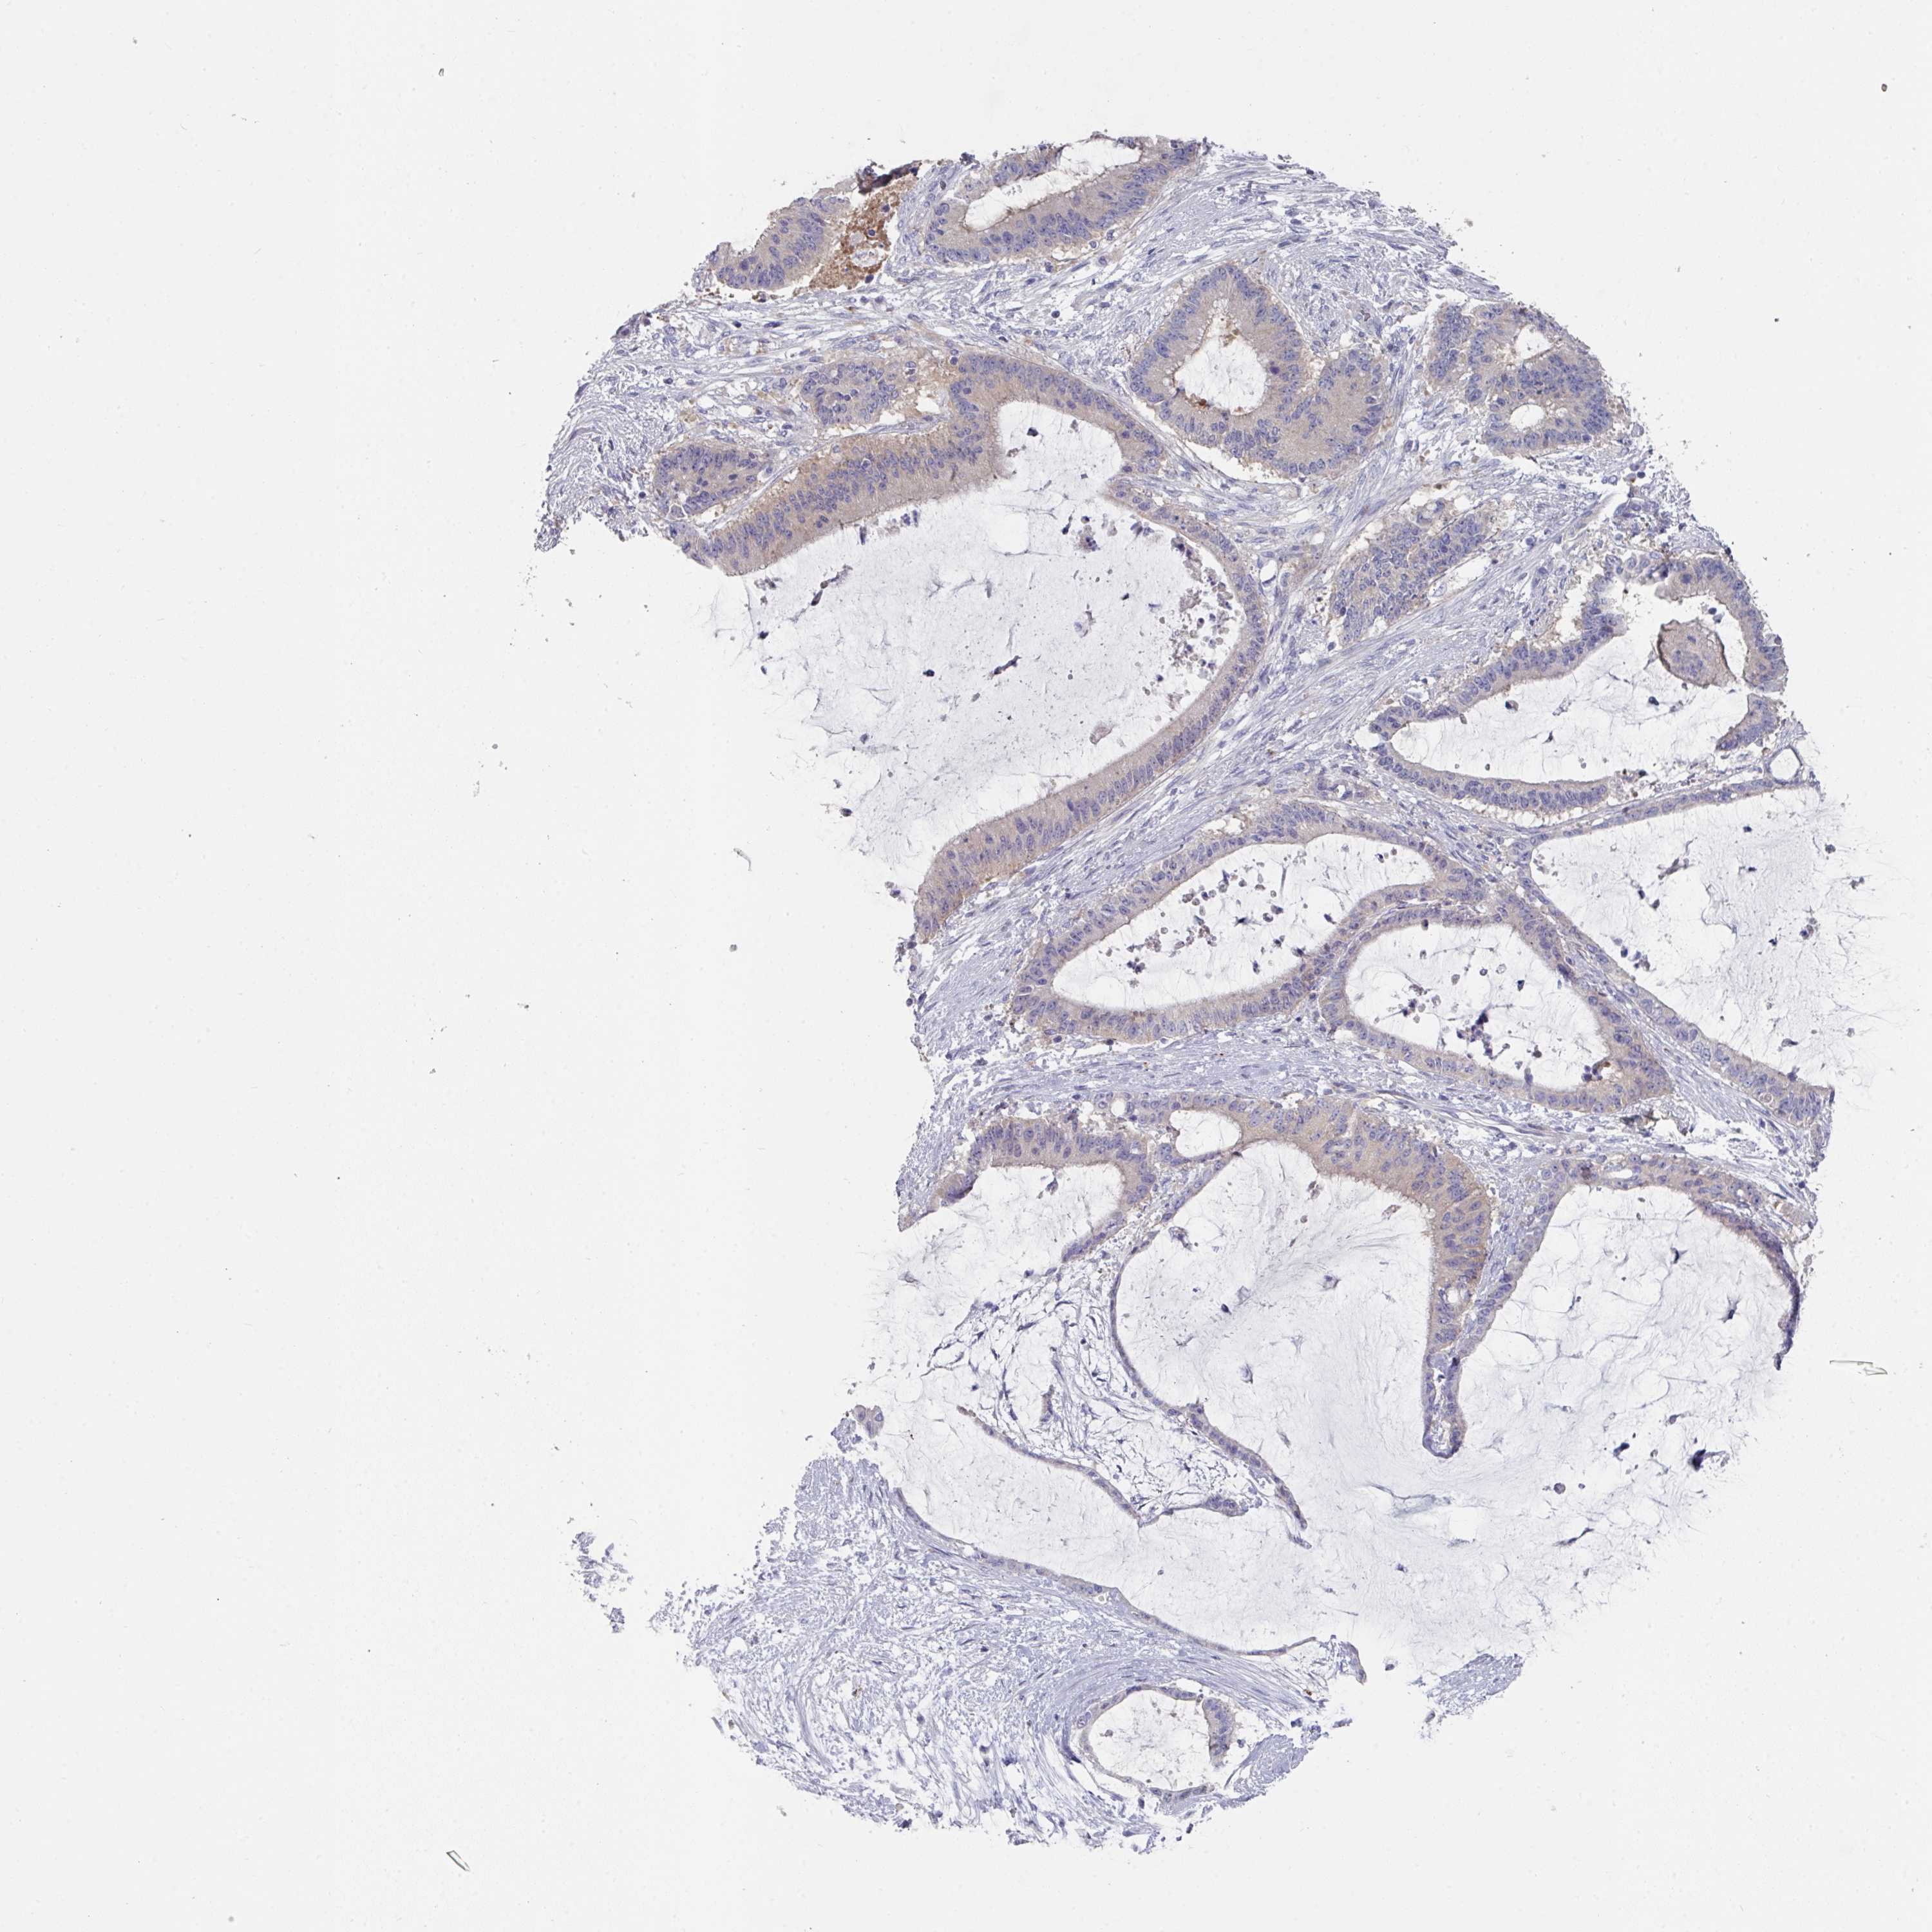

LIVER CANCER - Protein expressioni

A mouse-over function shows sample information and annotation data. Click on an image to view it in a full screen mode. Samples can be filtered based on level of antibody staining by selecting one or several of the following categories: high, medium, low and not detected. The assay and annotation is described here.

Note that samples used for immunohistochemistry by the Human Protein Atlas do not correspond to samples in the TCGA dataset.

Antibody stainingi

Antibody staining in the annotated cell types in the current human tissue is reported as not detected, low, medium, or high, based on conventional immunohistochemistry profiling in selected tissues. This score is based on the combination of the staining intensity and fraction of stained cells.

Each image is clickable and will lead to virtual microscopy that enables deeper exploration of all samples and also displays staining intensity scores, fraction scores and subcellular localization as well as patient and tissue information for each sample.

Antibody HPA054158

Staining

High

Medium

Low

Not detected

Intensity

Strong

Moderate

Weak

Negative

Quantity

>75%

75%-25%

<25%

None

Location

Nuclear

Cytoplasmic/membranous

Cytoplasmic/membranous,nuclear

Cholangiocarcinoma